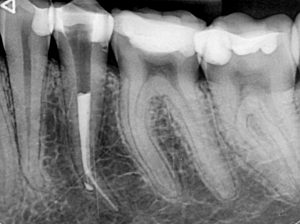

Перфорация на зъбен корен, съчетана със счупен инструмент

Случай на релечение на долен пети зъб, в който предишният колега беше фрактурирал канален инструмент и в опита си да довърши лечението бе перфорирал и корена на нивото на извивката. Освен перфорацията, извивката и счупения канален инструмент, сложността на случая идваше и от факта, че коренът беше изключително тесен в областта на извивката и имаше голяма опасност при премахването на инструмента зъбът допълнително да се отслаби на това място

След изключително щадящо премахване на инструмента, каналът бе обработен до невероятните 27 мм.

След което, заедно с перфорацията, беше запълнен с биокерамичен сийлър